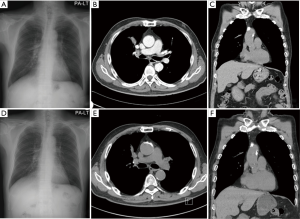

Two months later, the patient complained mild chest discomfort. And we performed chest CT again. There was no difference on the size of main mass and other metastatic nodules and lymph nodes. And four months after diagnosis, the patient didn’t receive chemotherapy still even in some herb medication, we performed chest CT again. Surprisingly, the size of main mass is reduced significantly from 5.4 to 3 cm and those of metastatic nodules were also reduced (Figure 2A-C). The patient took further five times chest CT in two month intervals thereafter to June 2014, main mass was reduced to 1.1 cm finally, and the size of metastatic lung nodules and lymph nodes were no change as compared with those of 2 months after diagnosis to date (Figure 2D-F).